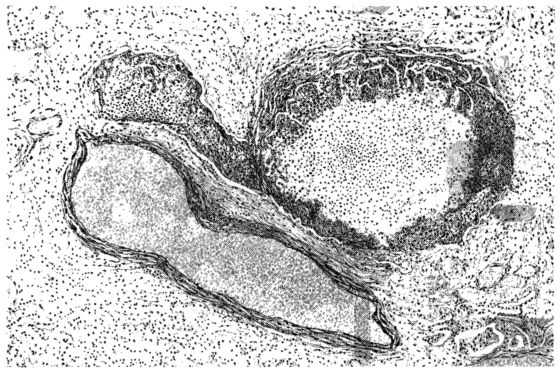

FIG. I. AUTOPSY NO. 99. ACUTE HEMORRHAGIC AND ULCERATIVE LARYNGOTRACHEITIS.

Early in the disease the congestion and the hemorrhages that have been described in the mucous membrane of the nasopharynx (14 and 94) are also conspicuous features in the lining of the trachea and bronchi (Fig. I). This membrane is swollen, turgid, red, and covered by a copious, mucous exudate which may be clear, but much more frequently is blood-stained or opaque and yellowish in color. The blood, variable in amount, may be fresh and red; and after the mucous exudate on the surface is removed, more intense red foci stand out on the congested base (47, 90, 157). Frequently, as the bronchi are approached, the red color of the mucosa becomes more intense and may have a garnet tinge. Membranes such as are encountered in the more usual necrotizing inflammatory processes, like diphtheria, have not occurred in the trachea and larger bronchi in this series (108, 128, 157).[3] The exudate peels off readily, and as indicated above, leaves a velvety red surface, 14dotted here and there with darker or more intensely red foci. Small ulcerations of the mucosa occur, but are inconspicuous (82, 156). As the finer ramifications of the bronchi are approached, the accumulation of the exudate in their lumina becomes more and more marked, and on cross section of the lung, they often stand out conspicuously on account of their increased size and projecting, seromucous, blood-stained content (101, 149, 162).